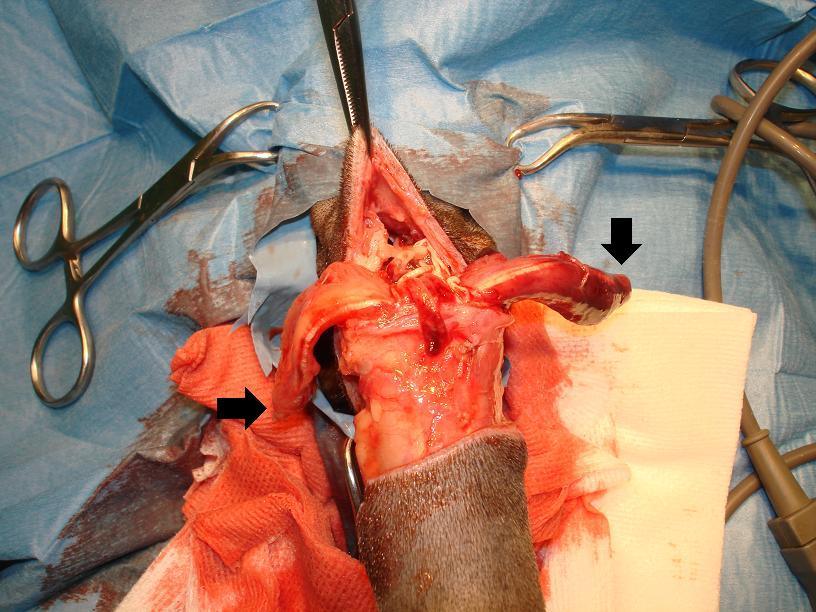

Po přípravě operačního pole, jsme odpreparovali kůži a podkožní tkáně, až do oblasti dutiny vyplněné tekutinou:

Následně jsme zjistili, že došlo i k úplnému utržení svalů (šipky), které spojují ocas se zbytek těla. Ty jsme postupně uvolnili, a odpreparovali zbytek ocasu.